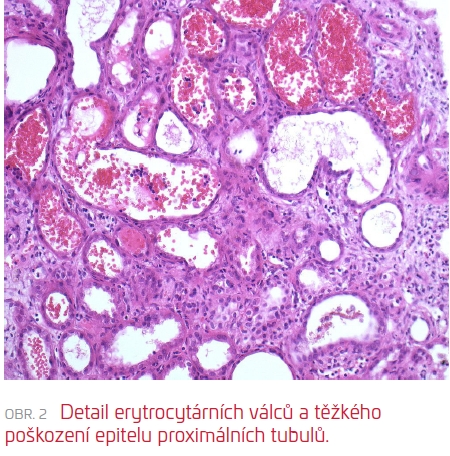

Následně (17. den od přijetí) byla provedena RB, která zachytila těsně subkapsulární punktát s morfologií akutní tubulární nekrózy s četnými čerstvými i lyzovanými erytrocyty/erytrocytárními válci v lumen tubulů, velmi pravděpodobně odpovídající antikoagulancii indukované nefropatii (viz obr. 1 a obr. 2). Současně byla diagnostikována glomerulonefritida s monoklonálními depozity (IgG, IgG3, C3 pozitivní), velmi suspektně jako součást prokázaného hematologického onemocnění (B‑NHL mantle cell lymfom). V subkapsulárním punktátu bez punkce arterií nebylo možné posoudit stav cév a rozsah spolupodílu vaskulární nefrosklerózy, který může limitovat další úpravu renálních funkcí.